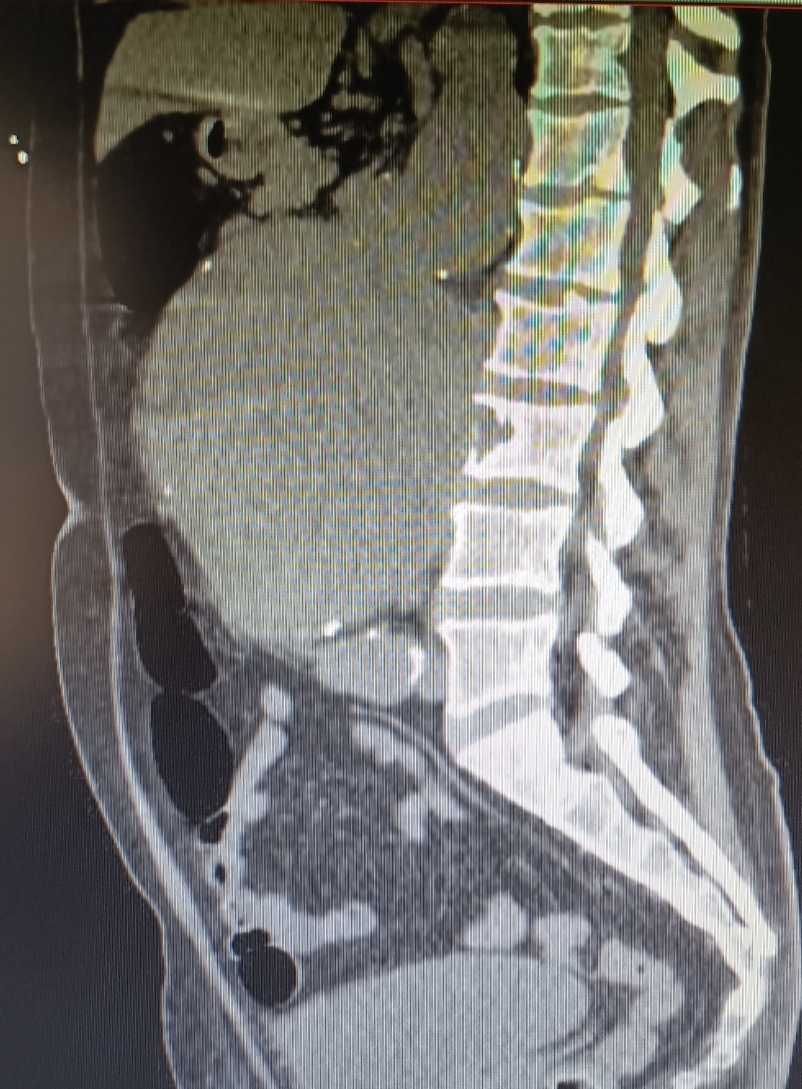

Se medica para control del dolor y se realiza Angio-TC de abdomen, donde se observan hallazgos compatibles con aneurisma de aorta abdominal infrarrenal de unos 14 x 13 cm que se extiende hasta bifurcación ilíacas, con calcificación intimal y trombo semilunar, con signos de rotura inminente.